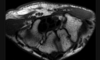

Cisto ósseo simples com fratura

Lesão litica unicameral.

Localização: úmero proximal e femur (< 20 anos) ou calcâneo, talus, ileo (> 20 anos).

Se fratura: Sinal do fragmento caído.